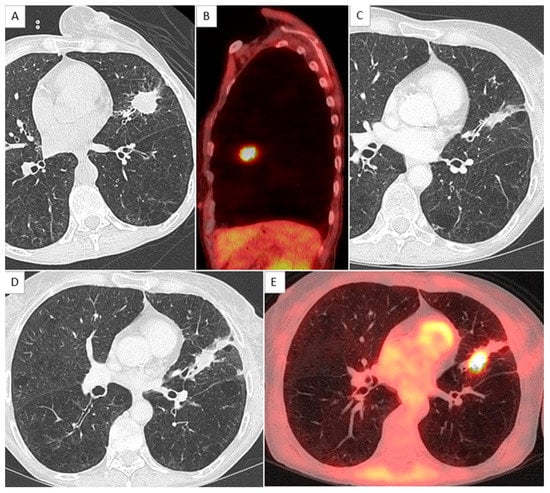

2.4. CT Scan Monitoring

2.5. Local Relapse Definition

- Kato, S.; Nambu, A.; Onishi, H.; Saito, A.; Kuriyama, K.; Komiyama, T.; Marino, K.; Araki, T. Computed tomography appearances of local recurrence after stereotactic body radiation therapy for stage I non-small-cell lung carcinoma. Jpn. J. Radiol. 2010, 28, 259–265. [Google Scholar] [CrossRef]

- Huang, K.; Dahele, M.; Senan, S.; Guckenberger, M.; Rodrigues, G.B.; Ward, A.; Boldt, R.G.; Palma, D.A. Radiographic changes after lung stereotactic ablative radiotherapy (SABR)—Can we distinguish recurrence from fibrosis? A systematic review of the literature. Radiother. Oncol. J. Eur. Soc. Ther. Radiol. Oncol. 2012, 102, 335–342. [Google Scholar] [CrossRef] [PubMed]

- Huang, K.; Senthi, S.; Palma, D.A.; Spoelstra, F.O.; Warner, A.; Slotman, B.J.; Senan, S. High-risk CT features for detection of local recurrence after stereotactic ablative radiotherapy for lung cancer. Radiother. Oncol. J. Eur. Soc. Ther. Radiol. Oncol. 2013, 109, 51–57. [Google Scholar] [CrossRef] [PubMed]

| Sequentially enlarging mass-like lesion | 12.0 | 1.2–120.1 | 0.034 | Yes | 1 |

| Craniocaudal growth | 19.2 | 1.8–199.9 | 0.013 | Yes | 1 |

| Bulging margin | 10.6 | 1.5–76.1 | 0.019 | Yes | 1 |

| SUVmax ≥ 5.5 | 11.0 | 1.6–73.9 | 0.014 | Yes | 1 |